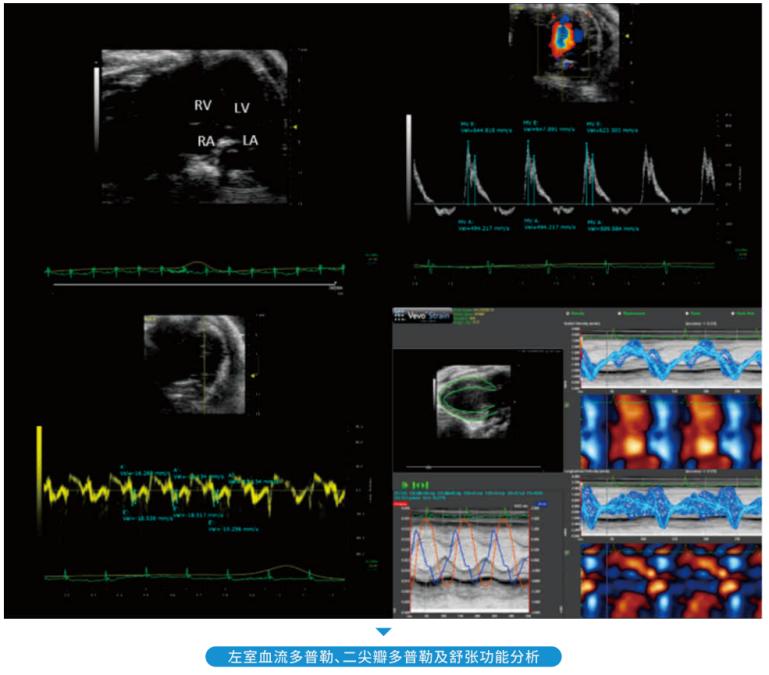

• 超高分辨率小动物超声

超高分辨率小动物超声

心血管系统、全身血管、腹腔、肿瘤研究、发育研究